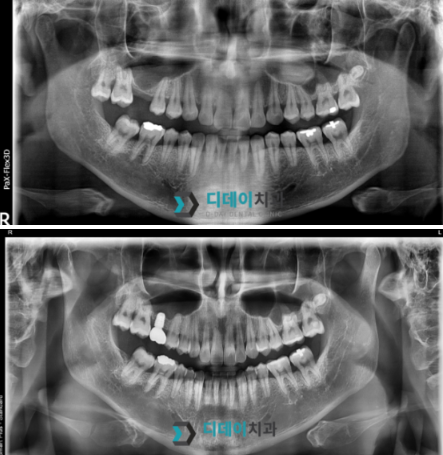

어금니 임플란트 치료를 위해 내원하신 환자분입니다.

오른쪽 위 어금니 발치한 상태로 내원하셨고

상악동 함기화로 인해 치조골이 부족한 상태였기때문에

상악동 거상술을 같이 진행했습니다.

저는 상담하실 때 3D CT 촬영을 통해

뼈의 높이, 폭, 밀도까지 꼼꼼하게 확인합니다.

그리고 그 결과를 환자분께 직접 보여드리면서

"이 부분은 뼈가 충분해서 바로 가능합니다"

혹은 "여기는 뼈이식이 필요합니다"라고

명확하게 설명해 드리죠.